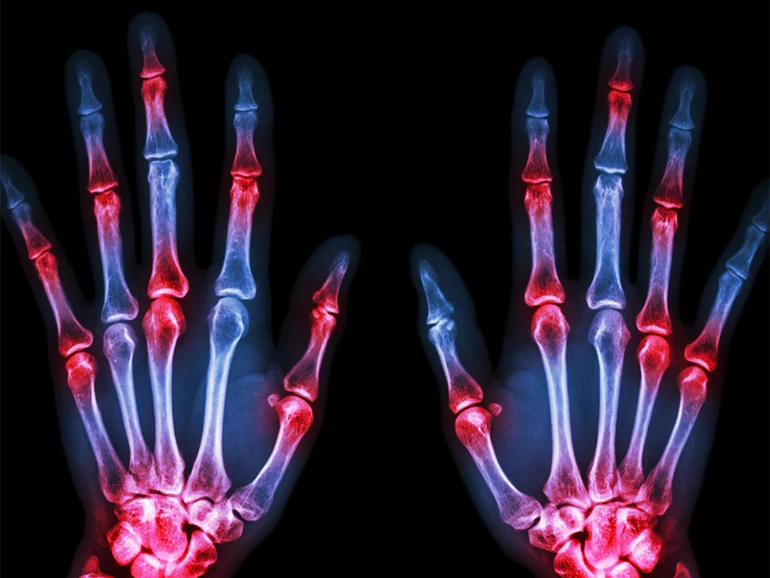

The focus of rheumatology is the joints, soft tissues, autoimmune illnesses, and heritable connective tissue disorders. It is a subspecialty of internal medicine. A rheumatologist is a medical professional who focuses on the diagnosis, therapy, and treatment of rheumatic disorders.

• Arthritis Patients – Pain, swelling, and stiffness in joints.

• Gout Patients – Sudden swelling and redness in joints.